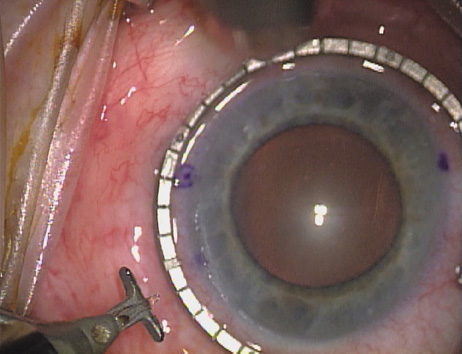

Case 1 is a 68-year-old male who presented for right cataract surgery. His refraction was −1.00 +2.25 × 80 and was recorded as reliable, consistent with his modest cataract density. Keratometry readings were 44.75 × 75 and 43.00 × 165. Corneal topography confirmed slightly more than 2.00 D of regular and slightly oblique cylinder. Consulting the nomogram, a plan was devised for a pair of LRIs to be centered over the 75-degree axis, with each incision delineating 45 degrees of arc. A single plane phaco incision was used and maintained at a size of less than 3.2 mm (Figs. 811).

Fig. 8. Steep meridian is confirmed intraoperatively by keratoscopy. In this left eye viewed from the temporal side, the “short axis” of the corneal mire is seen to be at the 75-degree meridian. (Reprinted from Hardten DR, Lindstrom RL, Davis EA. Phakic Intraocular Lenses: Principles and Practice. Thorofare, NJ: SLACK Incorporated, 2004, with permission.)